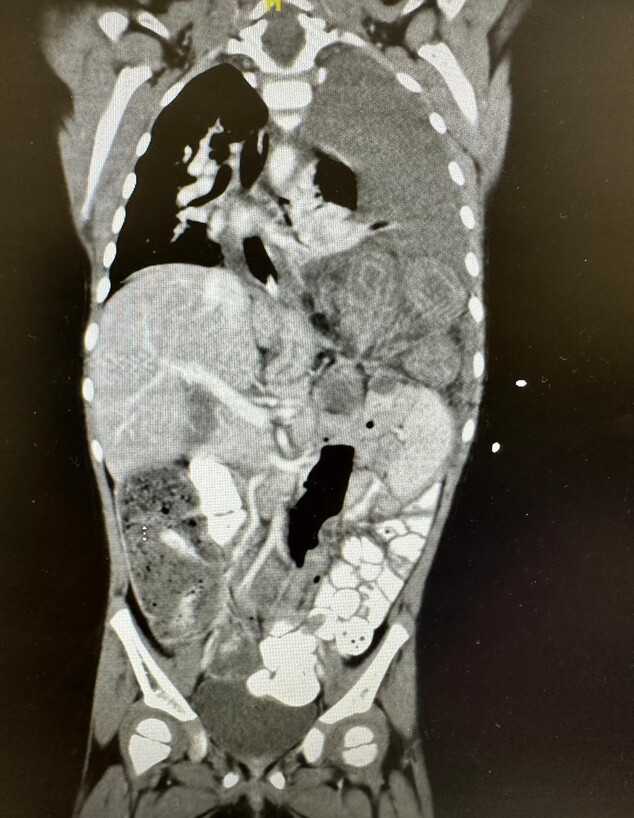

במחלקת הילדים הבחינה ד"ר סהר לזרי, רופאה בכירה ביחידה לכירורגית ילדים, בממצא מחשיד שתועד בצילום החזה שביצעה אלמה, ובעקבותיו, שלחה אותה לבדיקת CT דחופה - שבה התבררה הסיבה: הילדה סבלה מבקע סרעפתי חמור. "לולאות המעי שלה נדדו מחלל הבטן אל תוך החזה והיו כלואות שם - זהו מצב המסכן חיים באופן מיידי. כשראיתי את הצילום, היה לי ברור שגם אם יש טילים בחוץ - אנחנו נכנסים לחדר הניתוח באותו הרגע", היא מספרת.

בעוד קולות האזעקות והפיצוצים נשמעים ברקע, הוחלט שלא להמתין. אלמה הובהלה לחדר הניתוח הממוגן, שם ביצעו את הניתוח ד"ר איגור שייקיס, מנהל היחידה לכירורגיית ילדים במרכז רפואי צפון, יחד עם ד"ר סהר לזרי. כך הצליחו הרופאים לבצע את התיקון המורכב, להחזיר את המעי למקומו ולמנוע נזק בלתי הפיך לאיברים הפנימיים.

רק לאחר הניתוח התבררה התמונה המלאה: כאמור, במשך שנים סברו הרופאים כי אלמה סובלת מעיכוב התפתחותי פיזי, אך למעשה הקושי בתנועה נבע מכאב מתמשך ומאי-נוחות מכנית שנגרמה מהבקע הסרעפתי.